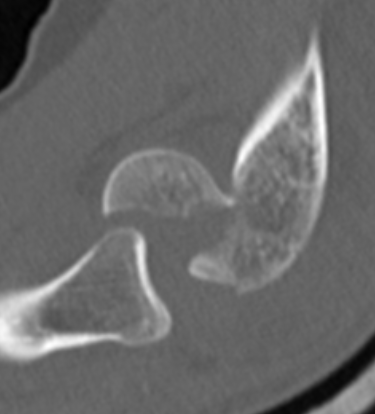

Coronal shear fracture of the distal humerus

Capitellum +/- trochlea

Large osseous fracture of the capitellum

Articular cartilage injury with little bone

Hanh Steinthal fracture

Kocher Lorenz fracture